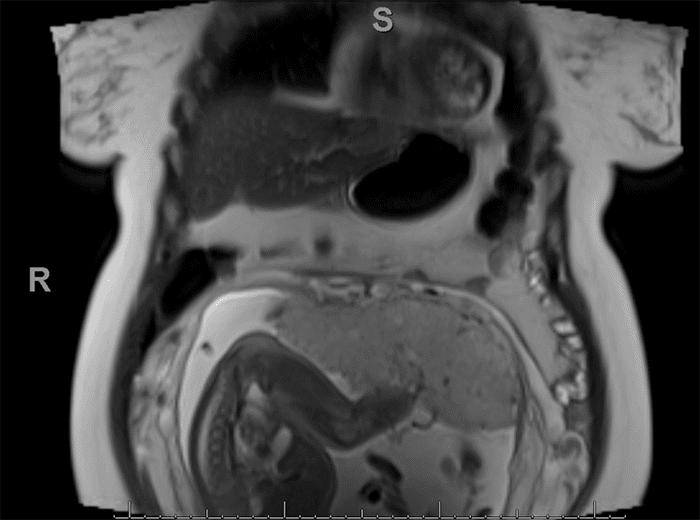

Biochemical testing at 31 weeks gestation revealed significantly elevated urine normetanephrine (4630 mcg/24 hour; normal 35-482 mcg/24 hour) and total metanephrine (4786 mcg/24 hour; normal 115-695 mcg/24 hour) levels, while catecholamine levels were within normal range. Subsequent magnetic resonance imaging (MRI) of the chest, abdomen, and pelvis revealed a 3.4 × 3.6 × 3.9 cm heterogenous mass in the right adrenal gland (Figures 1-3), consistent with pheochromocytoma.

Figure 1. Coronal View of T2-Weighted MRI (arrow indicating pheochromocytoma). Published With Permission

Figure 3. Sagittal View of T2-Weighted MRI Showing Patient at 31 weeks Gestation. Published With Permission